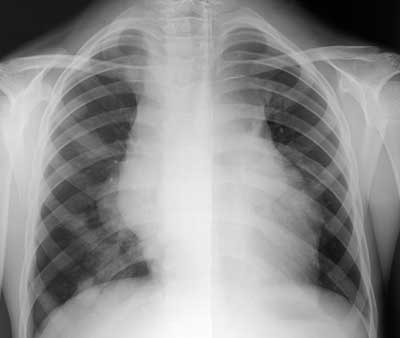

Лучевая диагностика неходжкинских лимфом у детей.

Рис. 1. Очаговые изменения в правом легком при неходжкинской лимфоме.

Новости лучевой диагностики 1998 5: 10-11